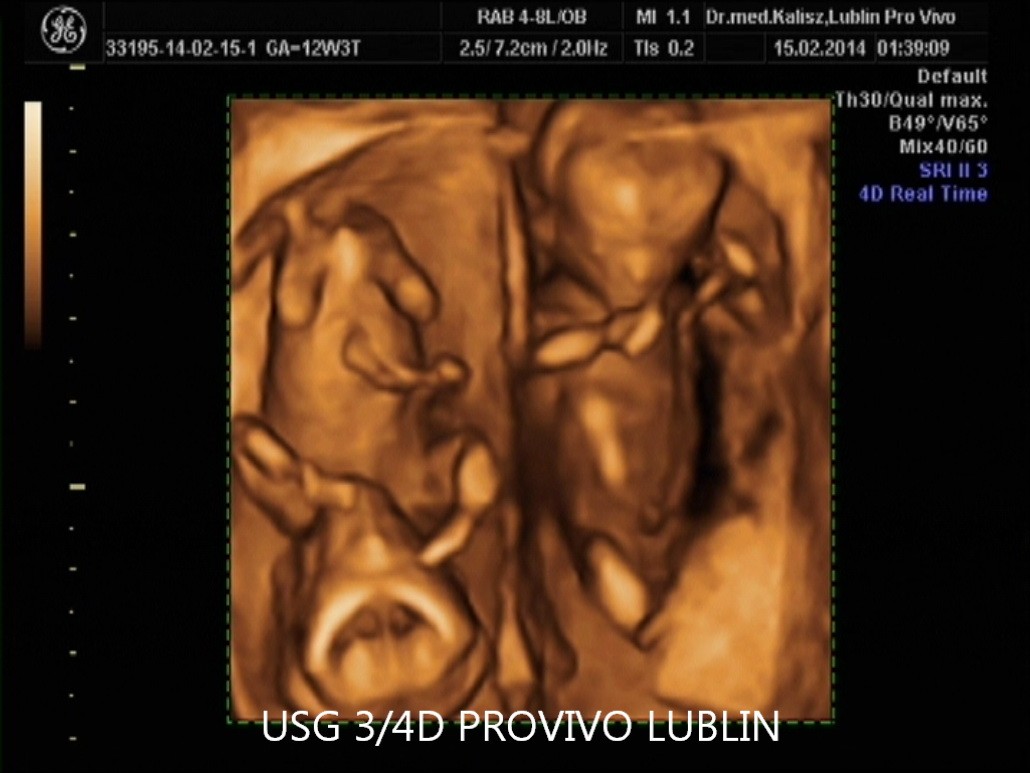

Urządzenia do USG 3D i 4D pokazują wyniki badania USG w sposób trójwymiarowy, dzięki czemu przyszli rodzice, zamiast jasnych i ciemnych plam na ekranie i zdjęciach, mogą zobaczyć swoje dziecko na żywo, zanim jeszcze pojawi się na świecie.

Aparaty do przeprowadzania USG 3D gwarantują trójwymiarową rekonstrukcję obrazu płodu i wnętrza macicy. Można w ten sposób zobaczyć powierzchnię zewnętrzną ciała rozwijającego się dziecka. Jego twarz ma dość wyraźny kształt, a rodzice, na pamiątkę badania, dostają zdjęcie z brzucha zapisane w formie elektronicznej na płycie CD.

USG 4D pokazuje obraz podobny jak w przypadku badania 3D, z tą różnicą, że jest to obraz dynamiczny, który zmienia się w czasie rzeczywistym. Przypomina to nieco podgląd na żywo, jak gdyby w macicy była umieszczona kamera.

Przyszli rodzice zobaczą w ten sposób ruchy dziecka, a także mimikę jego twarzy. Dla większości par jest to niezwykle wzruszająca chwili, kiedy po raz pierwszy mogą na własne oczy zobaczyć własne dziecko.

W trakcie ciąży takie badanie może być wykonane między 11-14 tygodniem ciąży, a potem około 20 lub 30 tygodnia.